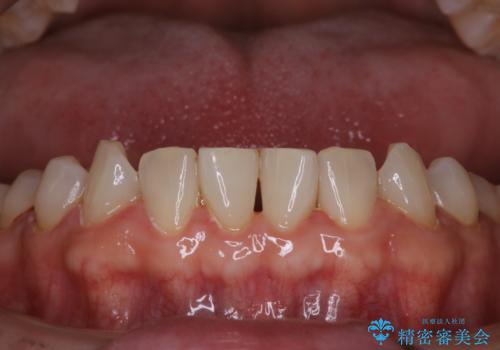

治療途中

お口全体に、歯垢・歯石が付着していたため、自費クリーニング(PMTC)60分コースを行い、徹底的に除去しました。

全体のチェックでレントゲン撮影も行いました。

40年ぶりの来院との事で全体的に、古くからの歯垢・歯石が硬く多く付着していたため、自費クリーニング(PMTC)60分1万円+TAXコースを行いました。